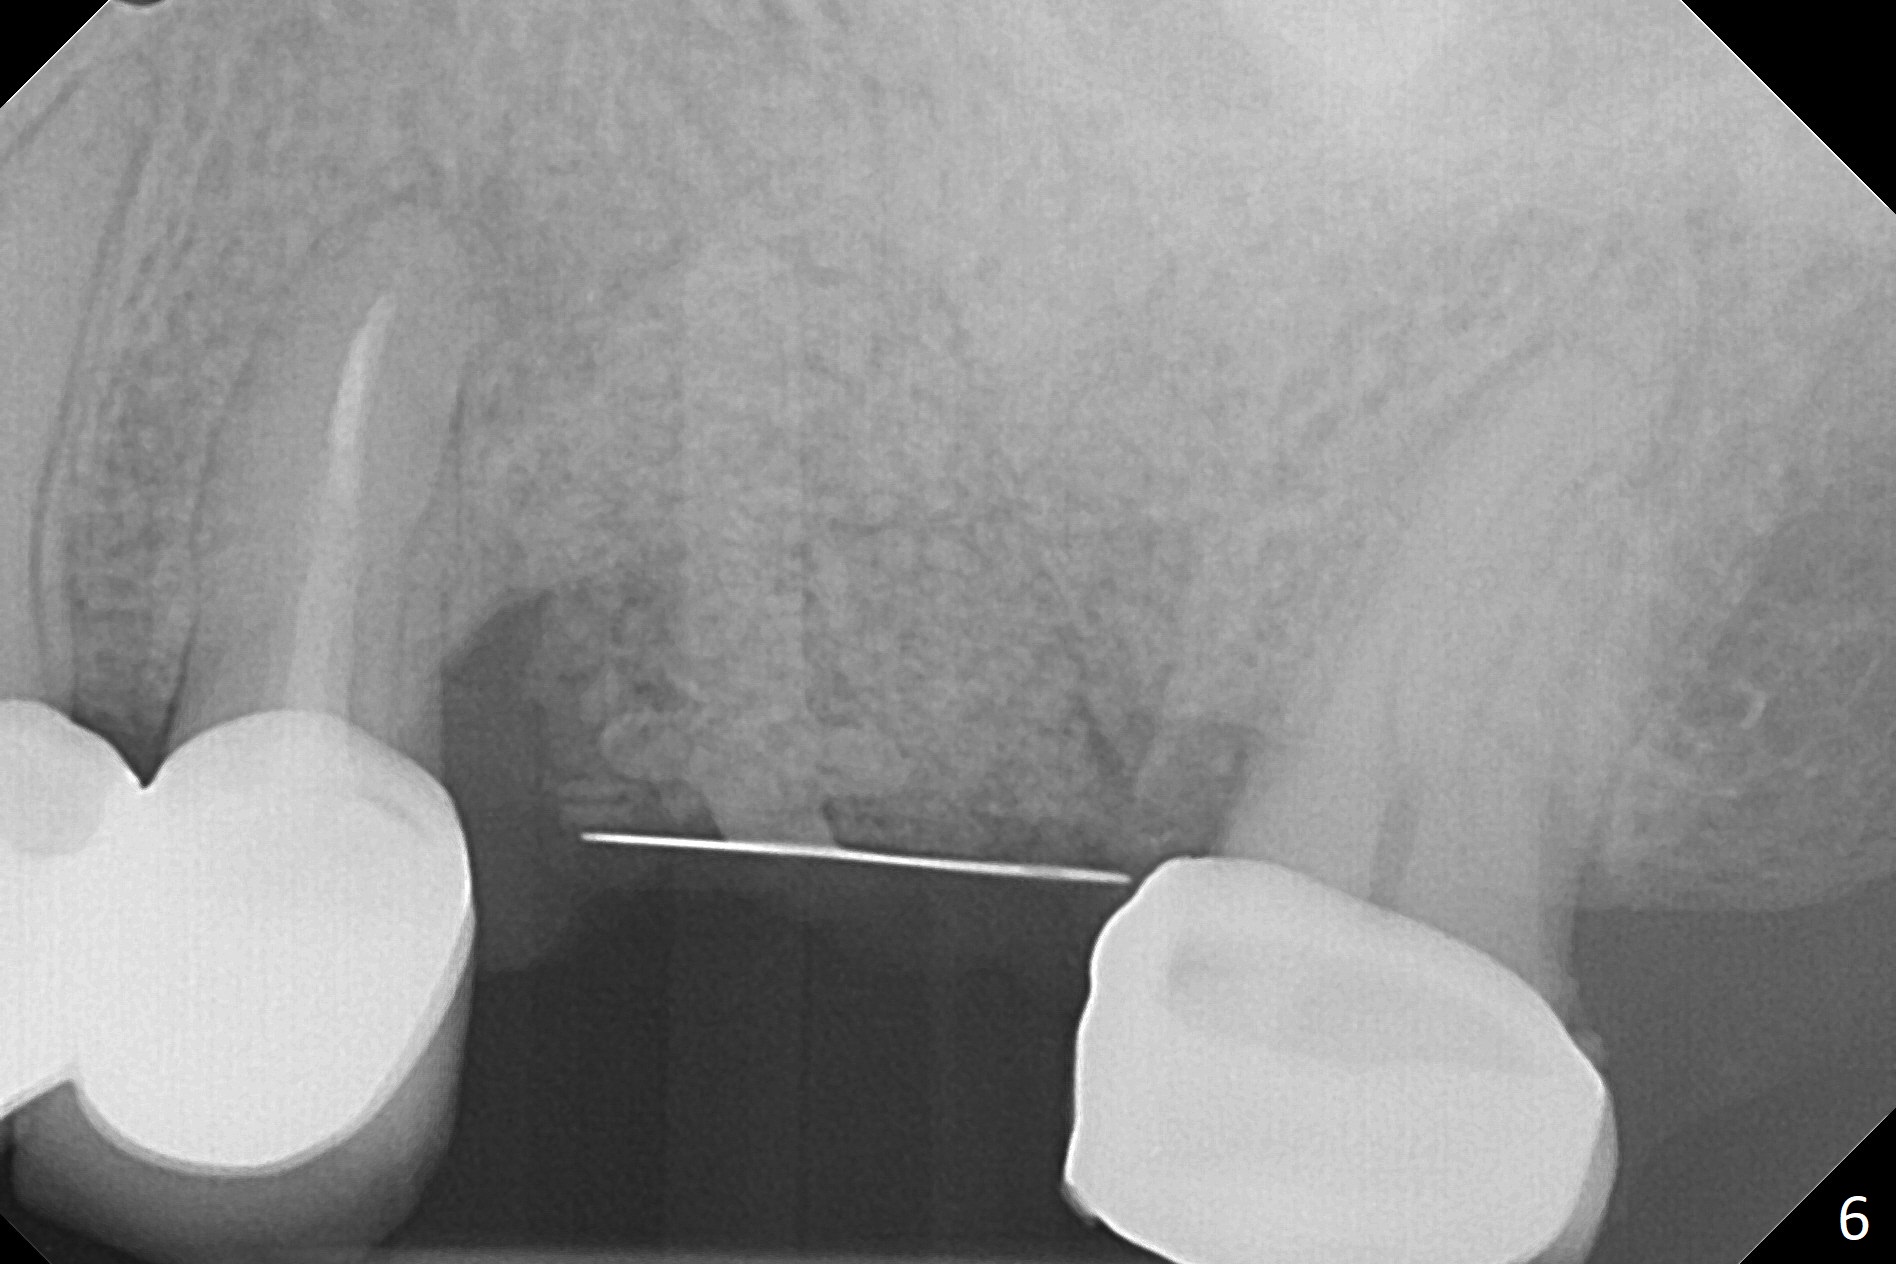

A 49-year-old woman returns for removal of the tooth #14 with loss of the buccal plate (Fig.1 red dashed line). After extraction, the buccal gingiva collapses as a dimple (Fig.2 ^). Cytoplast, a Titanium-Reinforced Non-resorbable Membrane (Fig.3), is used after bending (Fig.4) to assist in repair of the buccal plate with bone graft (Fig.5,6). As compared to Fig.1, the bone height also increases. Periodontal dressing and Cytoplast dislodge with odor 10 days postop (Fig.7,8). Periodontal dressing is re-applied. Spacer or acrylic dressing should have been used for security. In spite of the narrow ridge 5 months postop (Fig.9), a 5x11.5 mm bone level or 5x17 mm tissue-level implant is possible (Fig.10). But the implant should be placed more palatal, away from the buccal defect!